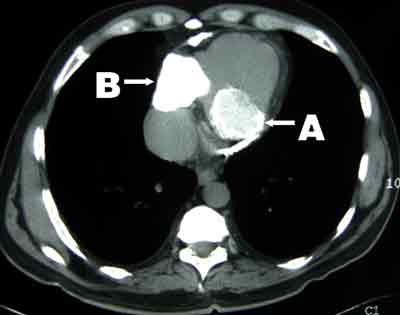

A 58-year-old man of British descent presented in 2003 with chest pain, facial flushing and elevated jugular venous pressure but no leg oedema. He had been exposed to tuberculosis in childhood, had a strongly positive tuberculin test and had been followed up in the tuberculosis surveillance program with regular chest x-rays, but had never been diagnosed with tuberculosis. Chest x-ray on presentation showed calcified plaques and masses in the pericardium and mediastinum (Box 1). Computed tomography revealed extensive calcification of the pericardium (Box 2). Coronary angiography showed 70% stenosis in the left anterior descending artery. Cardiac catheterisation showed equalisation of diastolic pressures in all four chambers, with a positive square root sign (pattern of ventricular diastolic pressure characteristic of constrictive pericarditis).